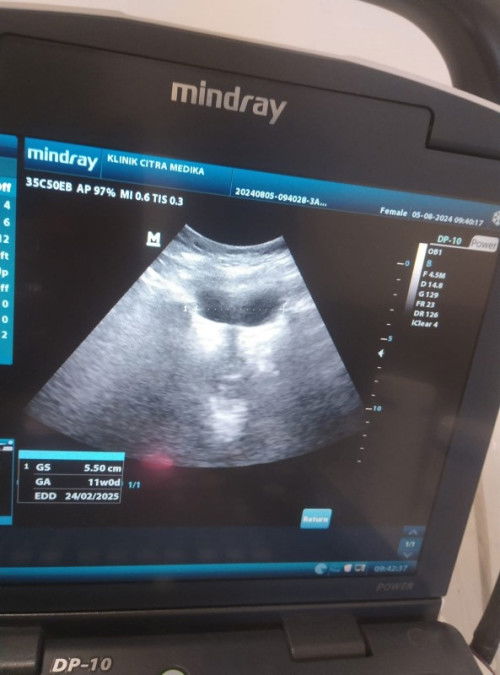

Usia kehamilan 5w

assalamualaikum bunda, saya mau bertanya hpht 30 Juni 2024 harus nya baru 5 Minggu tp td pagi saya USG ukuran kantong nya 5.50 cm dan klau berdasarkan ukuran kantong kehamilan saya udah usia 11 mnggu,yg JD pertanyaan saya normal atau gak usia 5 mnggu ukuran nya segtu, atau kah alat USG nya yg rusak ya bund..

itu GA 11w0D apa yha?